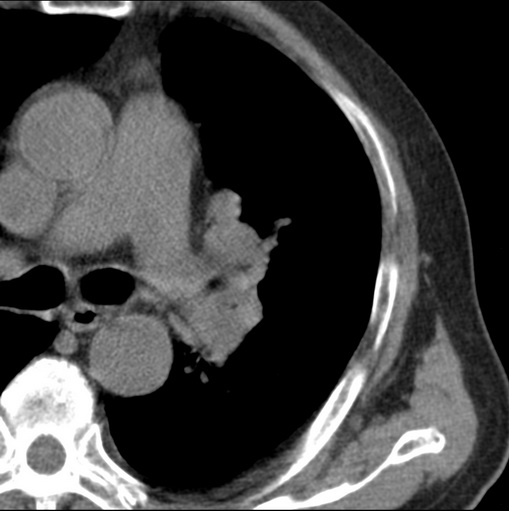

标题: CT25434:胸部CT增强扫描

男性患者 81岁 咳嗽 咳痰 咯血

强化较典型,左上肺癌并纵膈淋巴结转移;左上肺结核并空洞形成;胸膜增厚.

肿块贴近左肺门,包绕左上肺动脉,形态不规则。肿块增强扫描中度强化。纵膈内主动脉弓左旁间隙、气管隆突前、下间隙见多枚淋巴结影。综上考虑左侧中央型肺癌可能性大。图片没有完整上传,尤其是左肺上叶支气管分支层面没有上传,因此不好判断是叶支气管中断还是段支气管中断。另外,下图红色部分所示是“黏液支气管征”吗?